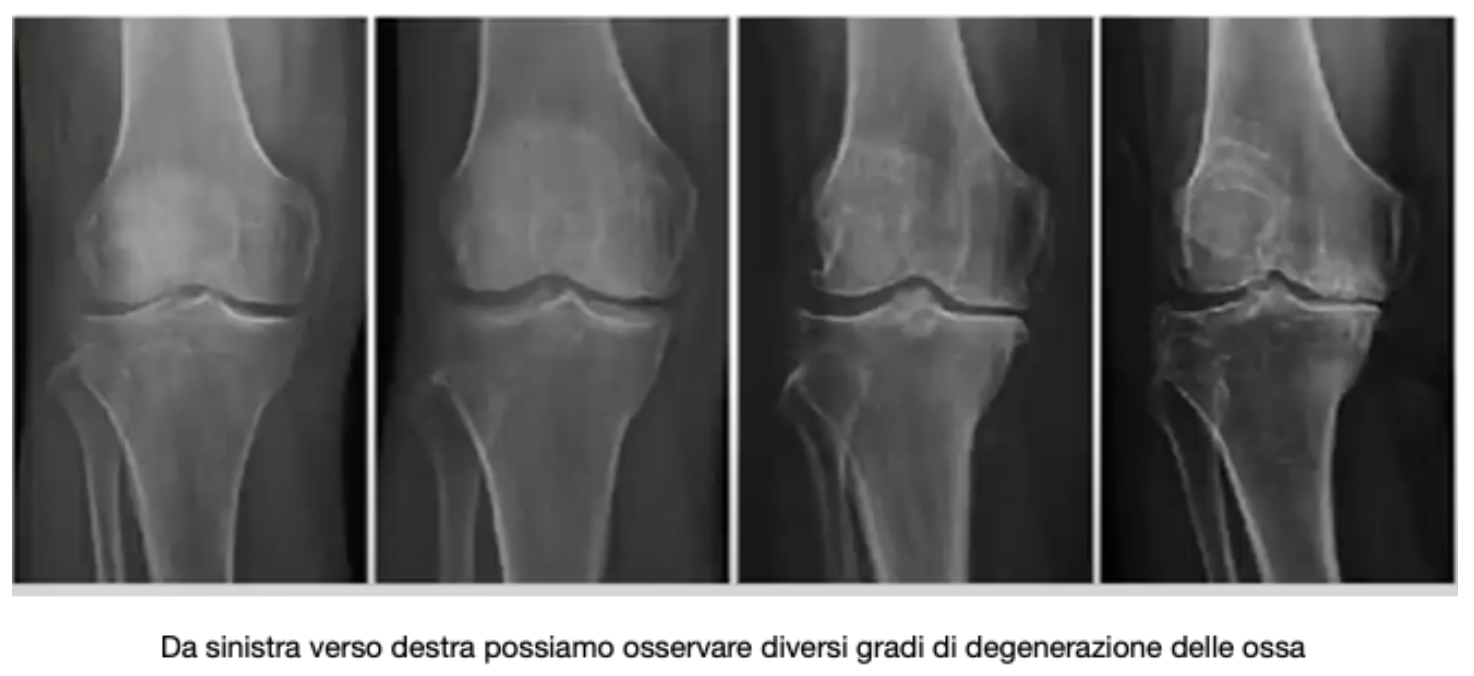

La Diagnosi

La Gonartrosi viene diagnosticata con una “radiografia sotto carico” con cui è possibile constatare il grado di deterioramento delle cartilagini; anche se la diagnosi risulta poco complicata una cura definitiva ad oggi non esiste e solo nei casi di maggior gravità vengono effettuate operazioni applicando al ginocchio una protesi.